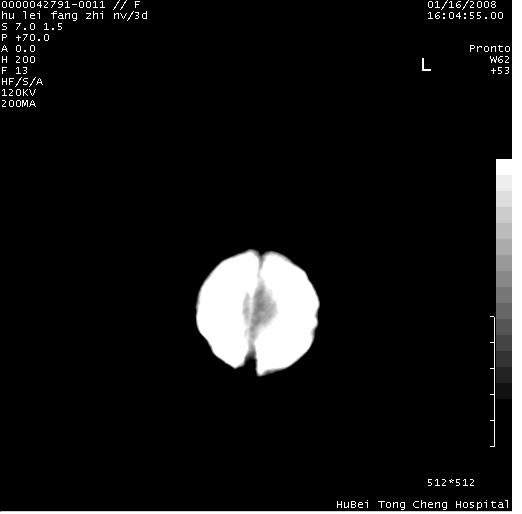

患儿 女,3天。惊跳,纳差。第二胎顺产,羊水ⅱ度。

临床诊断:hie?

颅脑ct轴位平扫(层厚、层距均为7mm),图像如下:

支持胼胝体发育不良。

支持hie,胼胝体发育差些

支持胼胝体发育不良